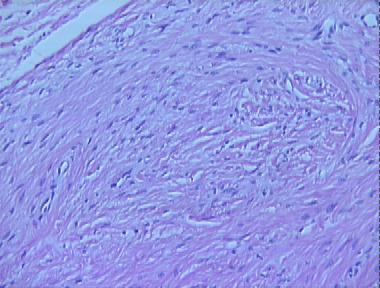

ancient neurofibroma

Histologic Features